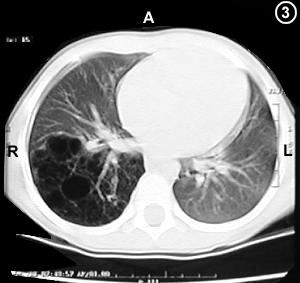

Corte Tomográfico " 3 "

Corte 4 cm. mas bajo al corte N°1:

Parenquima pulmonar del lóbulo inferior totalmente constituido de quistes.

Evidentemente este lóbulo ventilado durante la respiración, no participa en la hematosis sanguínea, convirtiendo en un agente compresor y de atelectasia de la estructura pulmonar sana.